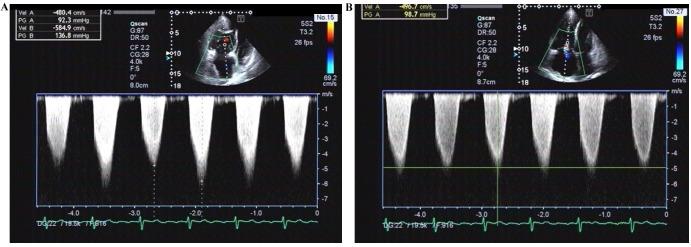

The present study aimed to evaluate hemodynamics and right ventricular function in patients with pulmonary hypertension (PH) using transthoracic echocardiography and to compare these results with measurements obtained using right-sided heart catheterization (RHC). A total of 75 patients with PH were examined using echocardiography and RHC. Patients were divided into the following two groups according to their difference between SPAP and SPAP measurement: The overestimated group and underestimated group. The overestimated group included the subgroups group (difference <20 mmHg) and group (difference ≥20 mmHg), and the underestimated group included group (absolute value of the difference <20 mmHg) and group (absolute value of the difference ≥20 mmHg). SPAP measurements were revealed to be significantly positively correlated with SPAP measurements (r=0.794; P<0.01). Among all echocardiographic measurements, only tricuspid annular plane systolic excursion (TAPSE) was significantly different between groups; it was increased in group and group compared with group (P<0.01). Although SPAP measurements obtained using echocardiography were significantly positively correlated with those obtained using RHC, a high proportion of overestimation or underestimation of SPAP by echocardiography remained.

本研究旨在使用经胸超声心动图评估肺动脉高压(PH)患者的血流动力学和右心室功能,并将这些结果与使用右心导管检查(RHC)获得的测量值进行比较。共有75例PH患者接受了超声心动图和RHC检查。根据其收缩期肺动脉压(SPAP)测量值之间的差异,将患者分为以下两组:高估组和低估组。高估组包括亚组(差异<20 mmHg)和亚组(差异≥20 mmHg),低估组包括亚组(差异绝对值<20 mmHg)和亚组(差异绝对值≥20 mmHg)。结果显示,SPAP测量值与SPAP测量值显著正相关(r = 0.794;P<0.01)。在所有超声心动图测量中,只有三尖瓣环平面收缩期位移(TAPSE)在各组之间存在显著差异;与组相比,组和组的TAPSE增加(P<0.01)。尽管使用超声心动图获得的SPAP测量值与使用RHC获得的测量值显著正相关,但超声心动图对SPAP的高估或低估比例仍然很高。